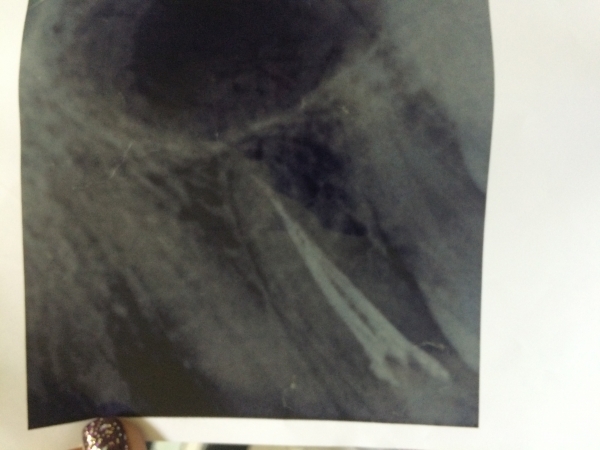

В феврале лечили верхнюю четверку слева, почистили полость и поставили пломбу. К вечеру зуб прострелило, появилось онемение и периодическая боль. Принято решение депульпировать. Все симптомы сразу исчезли. Неделю ходила с кальцием в каналах, в марте поставили постоянную пломбу. Месяц зуб практически никак не беспокоил, было ощущение чего-то инородного. Через месяц внезапно появилась боль и онемение по всем зубам слева сверху, но потом локализовалось в области четверки. На рентгене изменений нет. Боль усиливается, если появляется онемение, боль стихает. Субъективно, зуб кажется подвижным, хотя стоматолог это отрицает и утверждает, что с зубом все нормально. Зуб как будто в заморозке, есть отечность щеки и сглаженность носогубной складки. Невропатолог со своей стороны говорит о вторичной патологии, вызванной зубом. Сделала КТ, стоматолог утверждает, что все с зубом нормально.